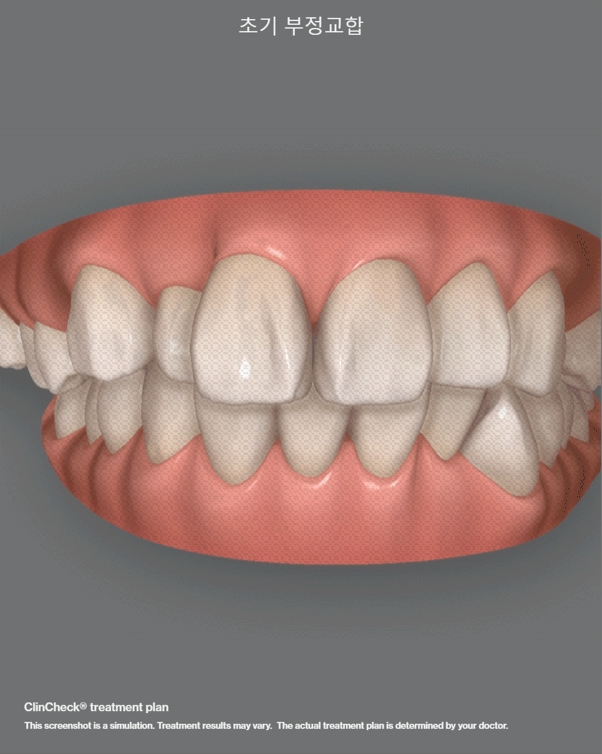

『인비절라인 정밀 진단』

클린첵 시뮬레이션에 따라서, 정밀진단을

진행했으며 치아들이 어떤식으로 이동이 되는지

가상 시뮬레이션으로 한 눈에 보실 수 있습니다.

앞서 말씀드린 것 처럼, 이 분은 발치 를

꼭 해야 좋은 결과를 낼 수 있기 때문에

환자께는 이런 사실은 분명히 안내드렸습니다.

근데, ‘뭐.. 해야 된다면 해야겠죠.’ 라면서

쿨하게 답변하셨던 분입니다.\

이렇게만 치열이 이동이 되면 소원이 없겠다는

환자의 말에, 그대로 재현을 해드리겠다는

약속을 드리면서 부정교합 교정치료에

들어갔습니다.